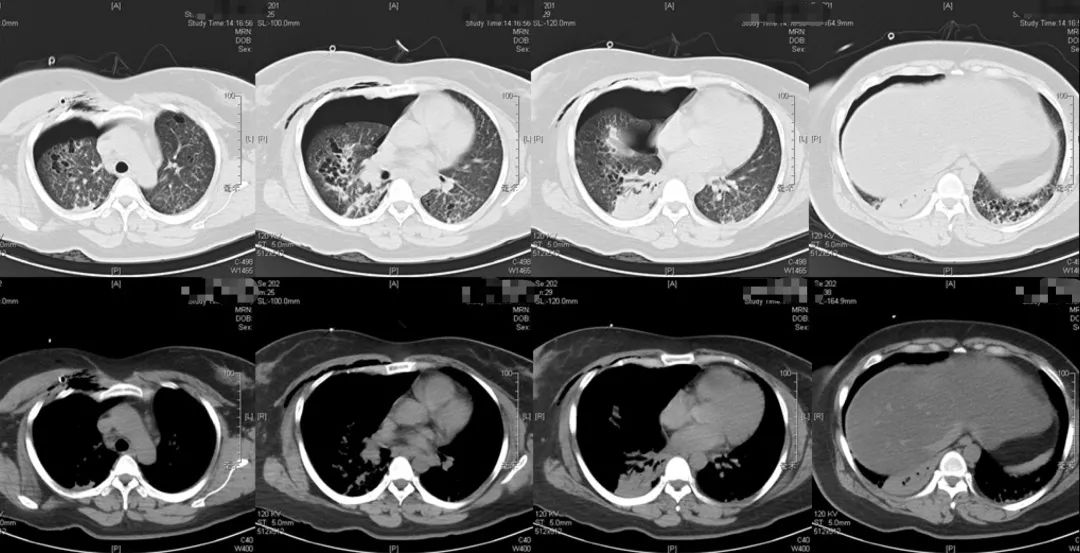

2019-5-14我院胸部CT平扫

患者青年女性,因「咳嗽、咳痰、咯血半月余,胸痛8天」入院,急性起病,逐渐加重,胸部CT提示右侧气胸,双肺相对弥漫分布的气囊与结节,沿气管血管束分布,右下肺实变。肺部弥漫性囊泡样疾病,需要考虑肺淋巴管平滑肌瘤病(LAM)、BHD综合征、肺朗格汉斯组织细胞增生症(PLCH)、淋巴细胞性间质性肺炎(LIP)、感染性疾病如耶氏肺孢子菌肺炎(PCP)等疾病。LAM一般常见于育龄期女性,影像学以弥漫均匀分布的薄壁囊泡为主要表现,此例患者为年轻女性,肺部多发囊泡,需要考虑LAM,但囊泡不是薄壁,分布不均匀,形状不规则,不符合LAM的典型表现。PLCH一般多见于吸烟患者,影像学以奇形怪状的沿支气管血管束分布的囊泡样改变为特点,吸烟患者一般以上叶及中叶病变为主,不累及肋膈角,多系统病变患者可以累及肋膈角,本例需考虑PLCH可能。BHD综合征肺部表现为多发薄壁囊肿,形状不规则,多于基底部、外周、沿纵隔分布,其他系统表现可合并皮疹、肾肿瘤等,可有家族史,本例患者无BHD家族史,需进一步排查其他器官有无病变。LIP常有肺部多发囊泡改变,一般合并自身免疫性疾病,该患者需进一步完善自身抗体等风湿免疫相关指标,协助诊断。此外,还需考虑PCP、金葡菌感染等感染性疾病。PCP多见于免疫抑制宿主,可以有多发性肺气囊的表现,该患者无发热,无免疫抑制病史,目*考前**虑可能性不大。

本例患者的胸部CT主要表现为两肺相对弥漫分布的怪异的气囊和结节,气囊为薄壁,以中上肺分布为主,沿支气管血管束分布,符合LCH细胞沿支气管分布的特点,并且有可能会引起支气管阻塞,类似活瓣样的作用,因此囊腔的形状怪异。胸腔镜术后的CT表现,可能是局部阻塞牵拉引起疱的加重,也可能是胸膜粘连后局限性的气胸的表现。